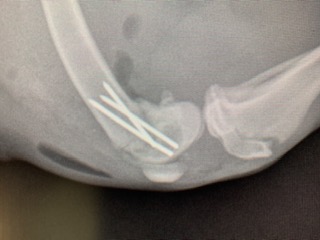

The Humane Society of Parkersburg reached out to Dr. Gandolf, who was able to surgically repair the femur- at a cost they could afford! The Animal Care Hospital of Reynoldsburg generously offered their operating room to help make this possible. This affordable alternative allowed the Humane Society of Parkersburg to save Marigold’s leg!

The Humane Society of Parkersburg was able to repair Marigold’s leg rather than amputate because of donations that fund these kinds of surgeries! Please consider giving TODAY to help Marigold and other dogs keep their legs!!